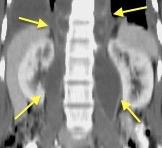

Líneas paraespinales formando un “paréntesis” por encima del diafragma. El signo señala el origen “intratorácico” de la lesión.

Conrad A et al. Pott’s disease associated with large and multiple abscesses in a 30-year-old migrant from Chad. BMJ Case Rep 2018

(lesiones toracoabdominales) La divergencia de las líneas paraespinales apunta a lesión toracoabdominal, que desde el tórax desciende y penetra en el abdomen.

Signo del “iceberg” positivo en Tb vertebral

Afectación por vía hematógena. Región dorsolumbar más frecuente. Afectación inicial: irregularidad de los platillos vertebrales, disminución del disco intervertebral con esclerosis ósea adyacente. Kim. Radiographics.2001